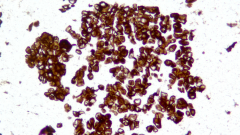

| Description | CLDN18.2是Claudin蛋白質(zhì)家族的一員,位于細(xì)胞膜表面,Claudin18.2(CLDN18.2)表達(dá)具有特異性。其作為Claudins蛋白的一個亞型,在正常組織中僅表達(dá)于分化的胃黏膜上皮細(xì)胞。在胃癌、食管癌和胰腺癌等多種腫瘤中表達(dá),并且不僅限于原發(fā)病灶,在轉(zhuǎn)移灶中也有表達(dá)。目前臨床研究中使用的檢測方法均為免疫組化。 |

| 示例 | ![]()  |

| IHC染色結(jié)果 | |